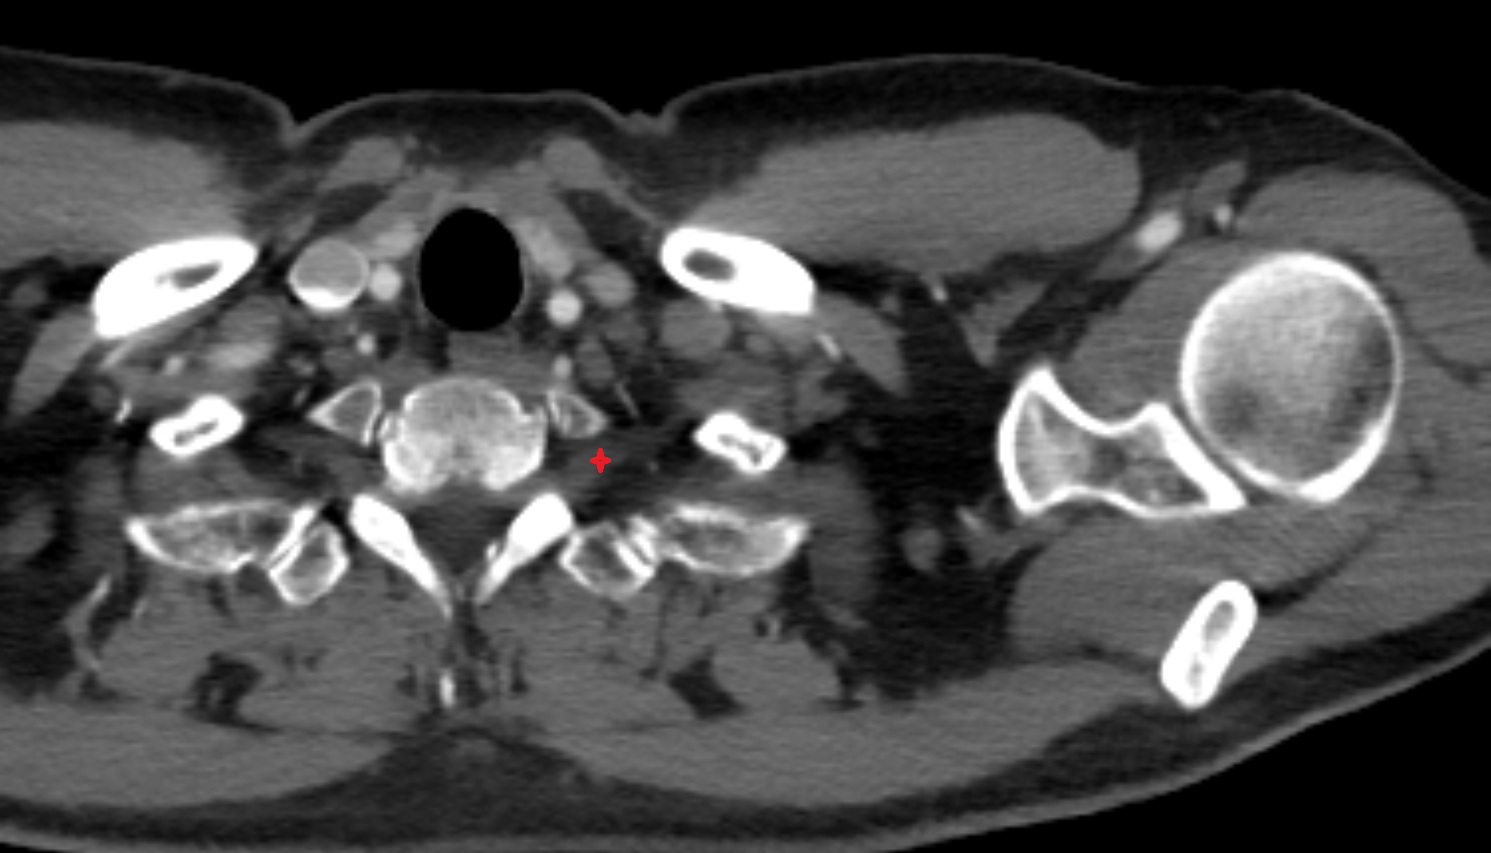

- Facet joint of vertebra (Zygapophyseal joints)

- Intervertebral Disc

- Anulus fibrosus of intervertebral disc

- Nucleus pulposus of intervertebral disc